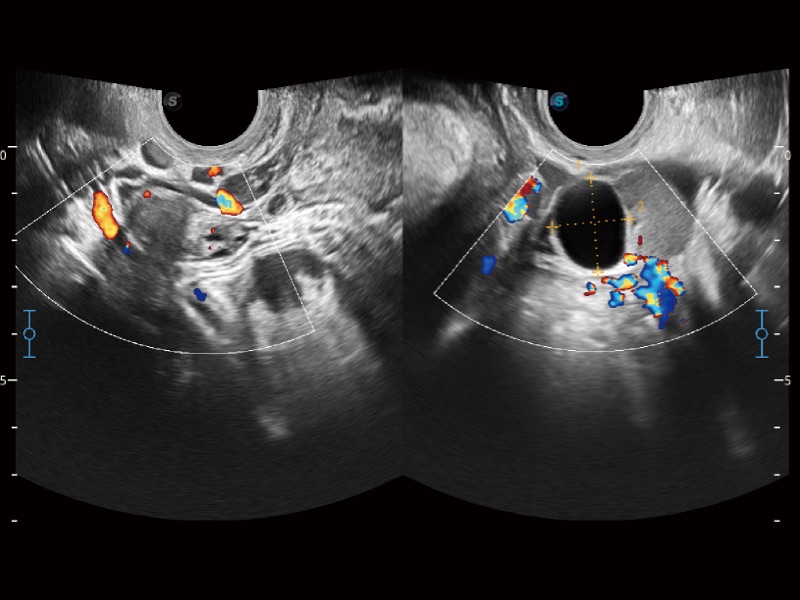

• 妇产科应用

• SR Flow 高分辨率血流成像技术

高分辨率血流成像技术提高了对低速血流信号的检测能力。在提高空间分辨率的同时,也克服了血流外溢现象,为用户提供更加真实的血流动力学信息。